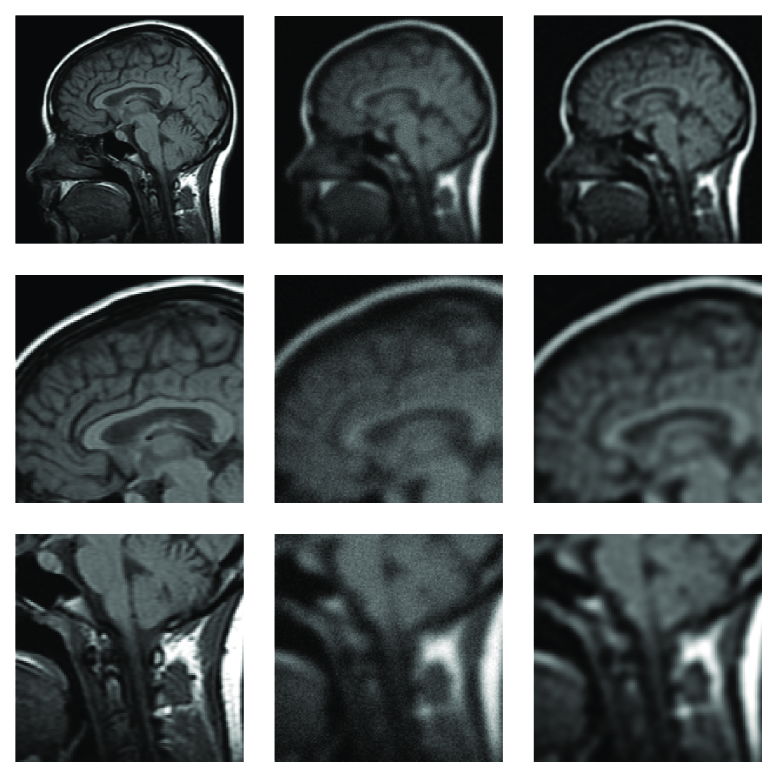

5.3 Results for MRI Reconstruction

The treatment of different kinds of medical images such as Magnetic Resonance Imaging (MRI), Computed Tomography (CT), Position Emission Tomography (PET), often requires the usage of image processing techniques to remove various types of degradations such as noise, blur and contrast imperfections. Our experiments focus on MRI medical image affected by Gaussian blur and noise. Typically, when blur and noise affect the MRI images, the visibility of small components in the image decreases and therefore image deblurring techniques are extensively employed to grant the image a sharper appearance.

In our test we blur a synthetic MRI image, with Gaussian blur (band=9, sigma=2.5), and we add 10% Gaussian white noise, since the noise level of a real problem may be expected to be quite high.

Figure 7 displays the performance of the algorithm. On the left column we show the blur-free and noise-free image, on the middle column we show the corrupted image, on the right column we show the restored image.The regularization operator employed is again (31). The result has been obtained in iterations of the algorithm, in around seconds.